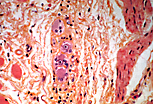

Ganglion

nerveux, coloré par un trichrome bleu où les fibres collagènes sont colorées en bleu

par le bleu d'aniline.

Bordées par les cellules satellites ganglionnaires, cellules de la névroglie périphérique, les cellules nerveuses ganglionnaires montrent les caractéristiques typiques des neurones. |